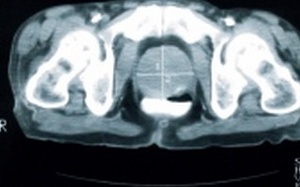

Nam giới vạm vỡ, sinh lý mạnh vẫn khó có con: Đâu là dấu hiệu cảnh báo?

Trong quan niệm của đại đa số nam giới, khả năng tình dục và khả năng sinh sản thường...